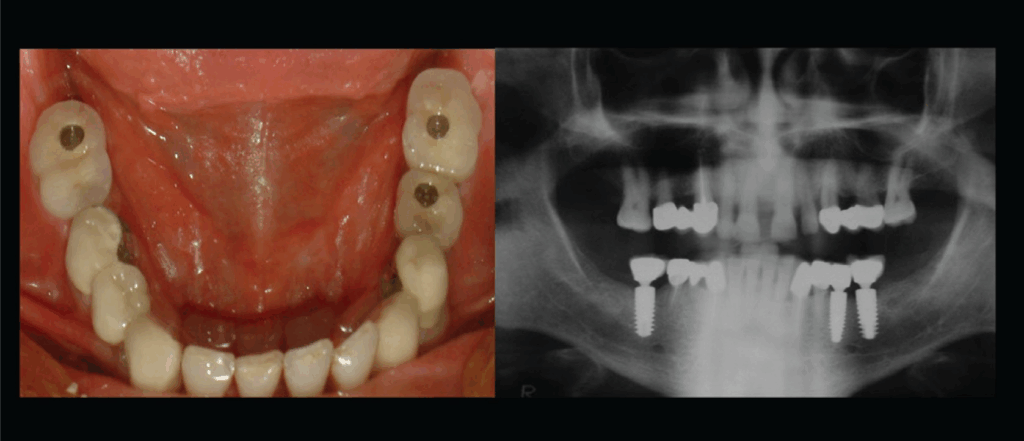

یکی از بزرگترین ریسک ها، پدیده ای به نام پری ایمپلنتایتیس یا التهاب اطراف ایمپلنت است. در این وضعیت، بافت های اطراف ایمپلنت دچار التهاب و تخریب استخوان می شوند. سیگار با کاهش جریان خون در این ناحیه باعث می شود که سیستم ایمنی دهان نتواند باکتری های مضر را به خوبی از بین ببرد و در نتیجه، التهاب تشدید گردد.

ریسک دیگر، شکست جوش خوردن ایمپلنت با استخوان یا همان Osseointegration failure است. نیکوتین و سایر مواد سمی موجود در دود سیگار مانع رشد سلول های استخوانی جدید می شوند. در بسیاری از افراد، پس از چند ماه، ایمپلنت لق می شود و نیاز به خارج کردن دارد. همچنین، احتمال سیاه شدن یا نکروز بافت های اطراف ایمپلنت نیز در افراد سیگاری بالاتر است. این وضعیت گاهی منجر به درد، ترشح، بوی بد دهان و از دست رفتن کامل ایمپلنت می شود.